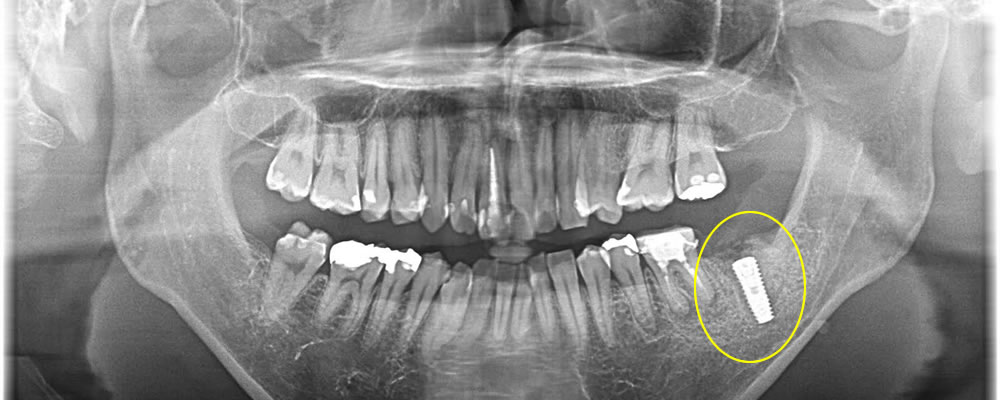

1つ前の歯も抜歯後に中を綺麗にし、インプラント埋入、骨造成までを1度のオペで行っていきました。こちらはインプラントの蓋が外に出るような形にして縫合しました。

上部構造の装着/治療完了

このオペが終わってから4ヶ月置き、しっかりと骨とインプラント体が結合している事を確認した後、上部の歯を作成していきました。

結果、綺麗な歯が出来上がりしっかりと噛む事ができるようになり、満足して頂く事ができました。